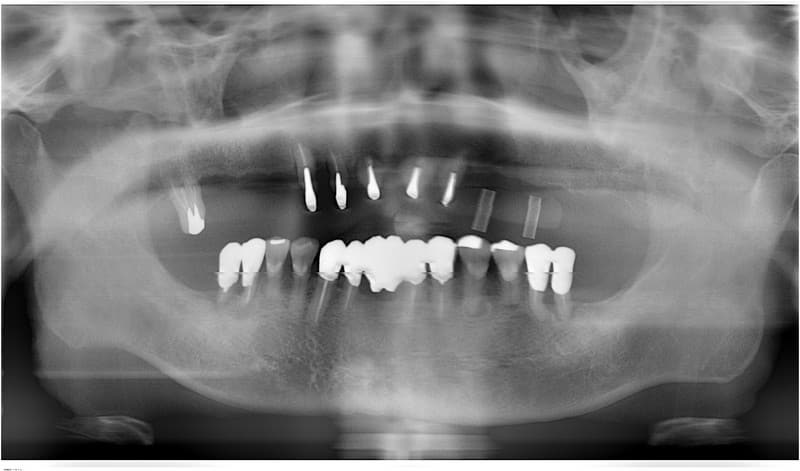

インプラント治療の流れ

インプラント治療に関する相談と説明

病歴や健康状態に関する問診、口の中の検査、レントゲン写真や歯型の採取

治療方針、計画の決定と説明

- 外科処置によって顎の骨にインプラントを埋め込みます。

- 3~6ヶ月後にインプラントに人工の歯を連結するためのパーツを取り付けます。

(小外科処置を伴います。)

技工士さんがあなただけの人工の歯をカスタムメイドで製作します。

人工の歯をインプラントに連結して完成となります。